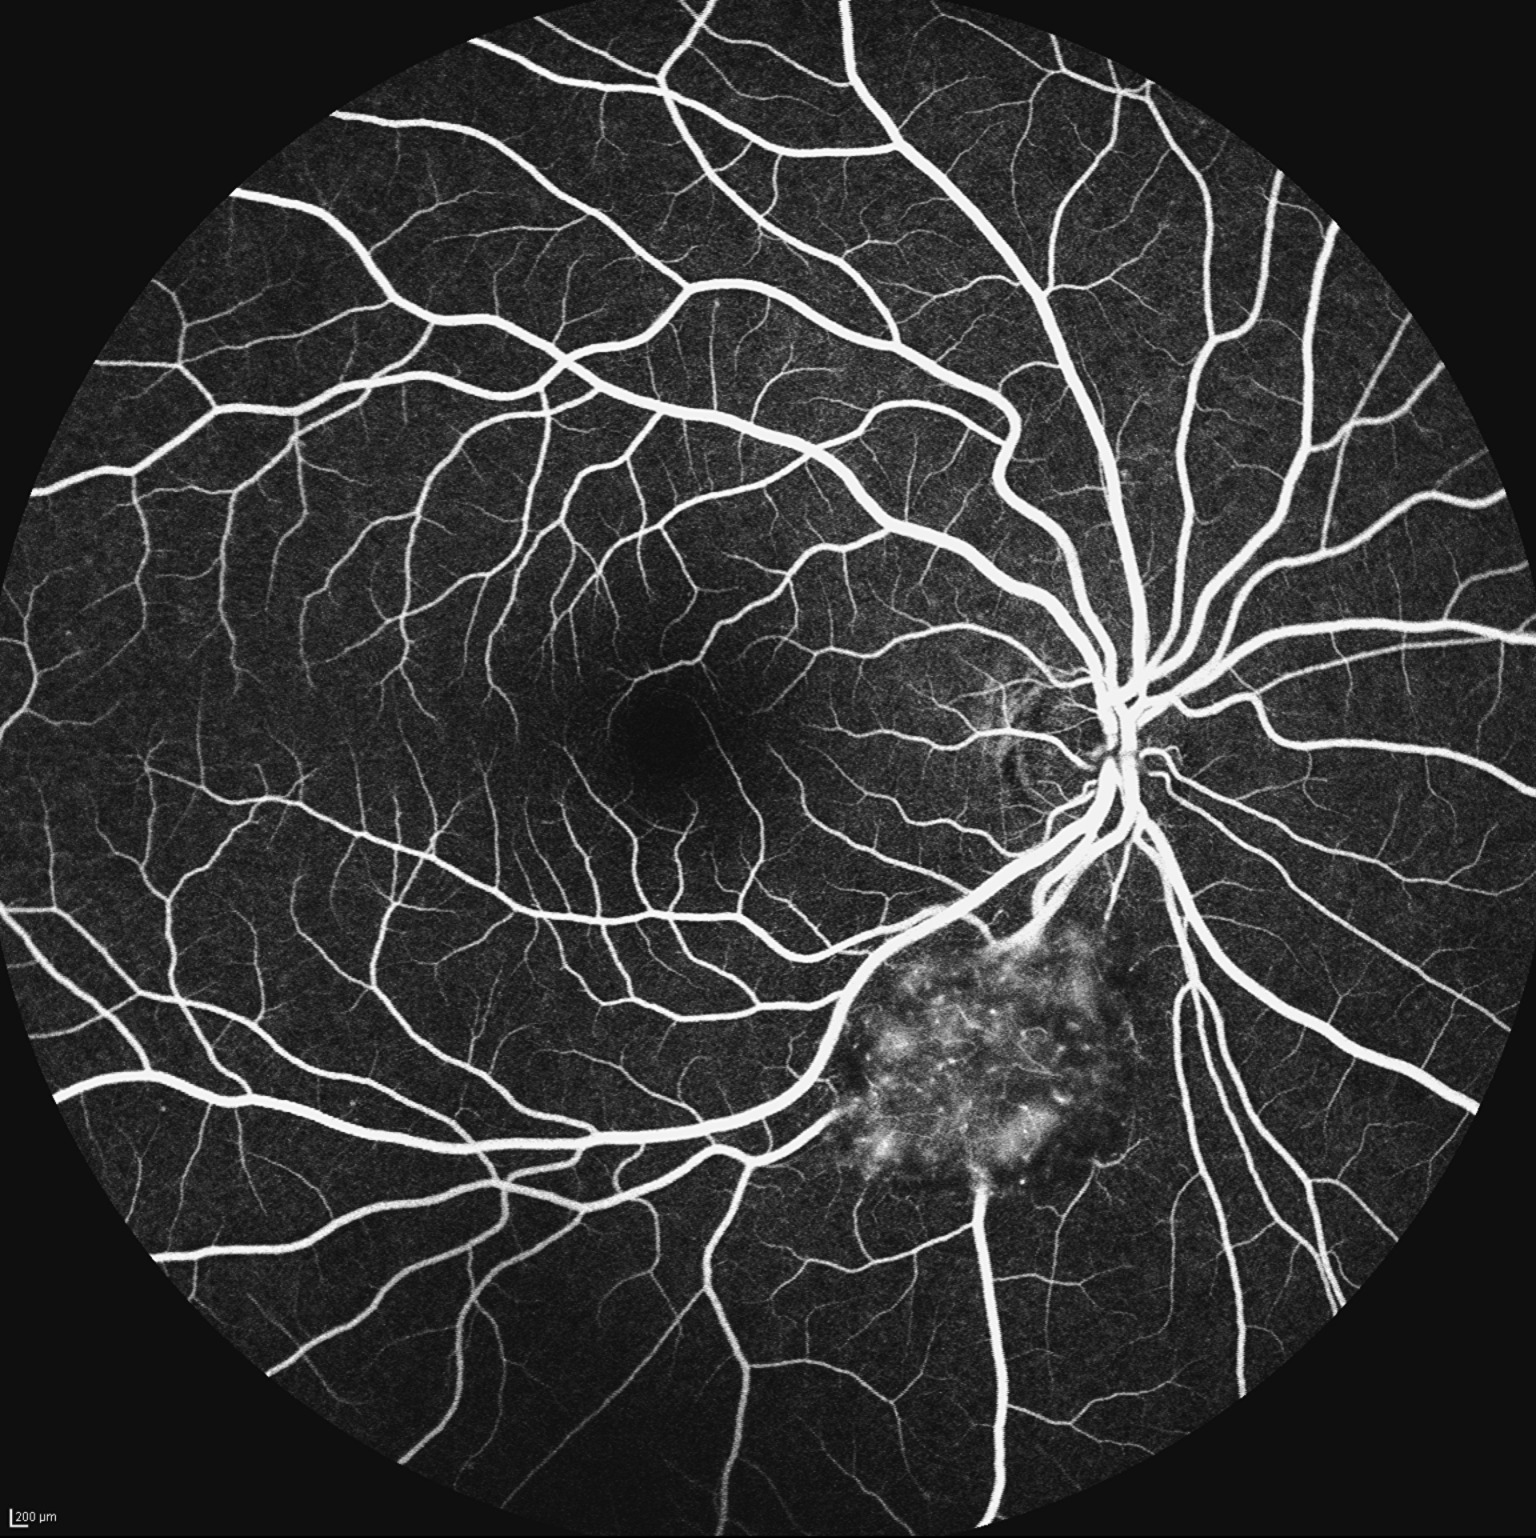

Nebula of Astrocytoma

Patient came with chief complaint of floater in right eye. On dilating, a lesion was found along ST vessel arcade. On FA using Heidelberg Spectralis HRA, a striking starburst of hyperfluorescence, its mottled texture and hazy borders gave the impression of a nebula igniting within the eye. Delicate capillary networks inside weaving an intricate lattice, looking like hidden galaxies in human eye.